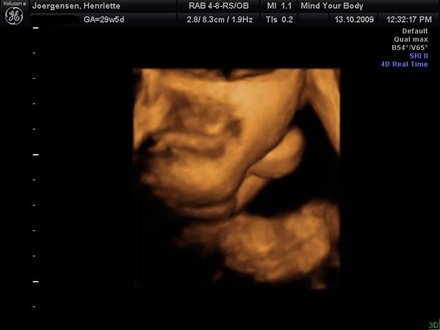

jeg har termin d 21 marts så der er lidt lid endnu

men tiden måtte godt flyve afsted så han kan komme ud til os